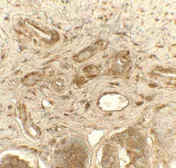

Product

Images